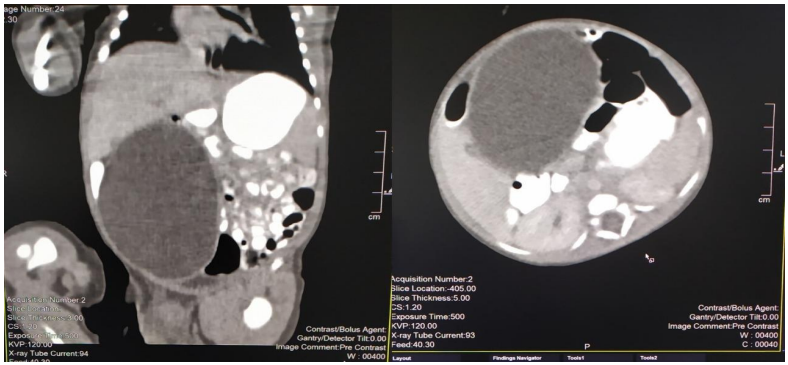

Figure 3. Gross macroscopic specimen

A 2815g 5-day-old male patient was born at 37.5 weeks gestation with an APGAR score of 9-10-10. An ultrasound scan identified an intra-abdominal lesion suggesting a megacolon diagnosis. After birth, further investigations revealed a large extrahepatic unilocular fluid-filled structure measuring 80x30 mm, suggesting a mesenteric cyst, cystic lymphangioma, or composite hepatic hamartoma. A cystic mass attached to the terminal ileum was noted at laparotomy, and the cyst and intestine were closely related. The ileon-cyst complex was resected and end-to-end interrupted primary anastomosis using vicryl 4/0 was performed. The gross pathological specimen showed a 75x10 mm intestinal fragment with ileal mucosa of normal appearance joined to a 80x35cm cystic structure containing mucus without luminal communication. The cyst contained mucus covered by glandular epithelial tissue and shared musculature with the intestinal portion, covered by gastric tissue. The cystic structure shared musculature with the intestinal portion, covered by gastric tissue within normal histological limits. The specimen was classified as Type 1B intestinal duplication according to the Long classification. The patient's post-operative period was uneventful, and at six months, he is thriving well without any complications.